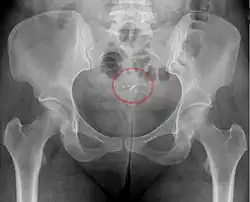

Mirena IUD visible on pelvic radiograph.

The hormonal IUD is a small T-shaped piece of plastic, which contains levonorgestrel, a type of progestin.[29] The cylinder of the device is coated with a membrane that regulates the release of the drug.[75] Bayer markets Skyla as Jaydess in the United Kingdom.[76] Jaydess releases six micrograms per day and lasts for three years.[77] In comparison, oral contraceptives can contain 150 micrograms of levonorgestrel.[53] The hormonal IUD releases the levonorgestrel directly into the uterus, as such its effects are mostly paracrine rather than systemic. Most of the drug stays inside the uterus, and only a small amount is absorbed into the rest of the body.[53]